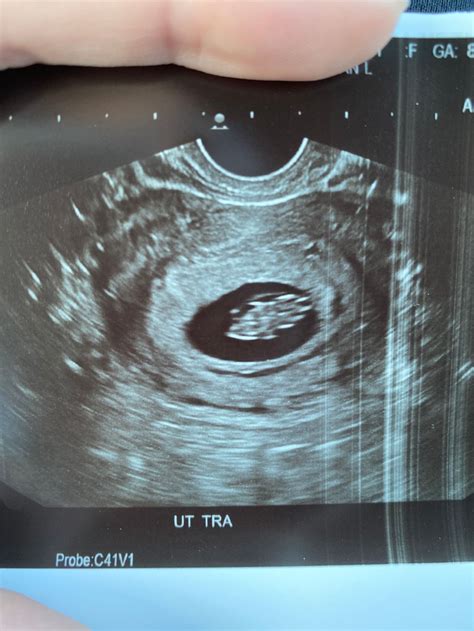

The 8 Week Sono is an ultrasound examination performed around the eighth week of pregnancy. This scan is typically done transvaginally, where a probe is inserted into the vagina to get a clearer image of the uterus and the developing fetus. The primary goal of the 8 Week Sono is to confirm the presence of a viable pregnancy, assess the fetal heart rate, and check for any early signs of potential complications.

• Gestational Sac: The gestational sac, which contains the developing embryo, should be visible. Its size and location are important indicators of a healthy pregnancy.

• Yolk Sac: The yolk sac, which provides early nutrition to the embryo, should also be visible. Its presence is a positive sign of a viable pregnancy.

• Crown-Rump Length (CRL): The CRL is the measurement from the top of the embryo’s head to its bottom. This measurement helps determine the gestational age and assess the embryo’s growth.

• Fetal Pole: The fetal pole, which is the earliest visible part of the embryo, should be visible. It appears as a small, curved structure within the gestational sac.

• Heartbeat: The fetal heartbeat should be detectable and visible on the ultrasound. This is a reassuring sign of a viable pregnancy.

• Amniotic Fluid: The amniotic sac, which contains the amniotic fluid, should be visible. This fluid provides a protective cushion for the developing fetus.